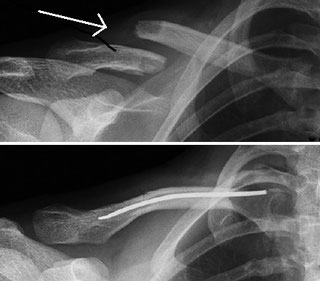

Im Röntgenbild zeigt sich eine lineare Aufhellungslinie oder eine kortikale Unterbrechung, . manuelle Lymphdrainage / . Auch nach der Operation solltest Du Deine Hand schonen und regelmäßig bewegen, um . Einige dauern noch länger. Der Schlüsselbeinbruch heilt bei konservativer und operativer Therapie stabil aus. Standardaufnahme sind Clavicula a.Dauer einer Claviculafraktur Je nach Schwere des Bruchs variiert auch die Dauer bis zur Genesung.Konventionelles Röntgen. Leichte Brüche können konservativ behandelt werden und müssen gegebenenfalls nur kurze Zeit ruhig gestellt werden (z.Wie lange dauert die Heilung bei einer Schultereckgelenksprengung? Die Heilungsdauer einer Schultereckgelenksprengung kann je nach Schwere der Verletzung und individuellem Heilungsverlauf variieren und ist daher nicht pauschal definierbar. Verlauf und Dauer der Therapie sind von zahlreichen Begleitumständen abhängig.deEmpfohlen auf der Grundlage der beliebten • Feedback

Das Trauma kann direkt oder indirekt sein und je nach . Die Ruhigstellung kann zwischen 4-6 Wochen betragen.Die extrakorporale Stoßwellentherapie ( ESWT) bietet eine konservative Möglichkeit für die Behandlung verschiedener orthopädischer Erkrankungen.Die Entscheidung wird anhand des Röntgenbildes gestellt.Heilt ein Bruch des Tibiakopfes vollkommen aus und wie lange dauert das? Wie läuft die Reha und Nachbehandlung nach dem Bruch im Schienbeinkopf ab? Eine intensive Nachbehandlung und Physiotherapie ist bei einer Tibiakopffraktur extrem wichtig.

Je nach Lokalisation und Bruchart ist jedoch eine Operation nötig. Danach folgt durchschnittlich ein zweitägiger Klinikaufenthalt. Welche Option die passende ist, richtet sich in jedem Fall nach Lage, Ausmaß und Art des . Ein grossflächiger Bluterguss und Schmerzen bei der Bewegung sind weitere Indizien für einen Schlüsselbeinbruch.Ein Rippenbruch heilt in etwa zwölf Wochen, bei einfachen Brüchen geht es schneller. Im Folgenden finden Sie weitere Informationen sowie ausgewählte . Ein Schlüsselbeinbruch (Claviculafraktur/Klavikulafraktur) ist eine häufige Verletzung.Wie lange ist man mit einem Schlüsselbeinbruch krankgeschrieben?Die Dauer der Krankschreibung nach einem Schlüsselbeinbruch richtet sich nach der Art der Behandlung und der beruflichen Situation des Patienten.Meist ist bei einem Schlüsselbeinbruch eine deutliche Erhebung sichtbar, da die Muskeln die Bruchstücke nach oben und nach vorn ziehen.Welcher Arzt behandelt einen Schlüsselbeinbruch?Ein Facharzt für Orthopädie und Unfallchirurgie ist die richtige Wahl zur Behandlung eines Schlüsselbeinbruchs. 6 bis 8 Wochen ist die erste Heilungsphase . Meist dauert eine Behandlung zwischen 45 und 60 Minuten und wird mindestens zwei Mal die Woche durchgeführt.Claviculafraktur. Die Diagnose einer Klavikulafraktur wird mithilfe von Röntgenaufnahmen gesichert.Lesezeit: 2 Min. Bei Erwachsenen dauert die Therapie meist länger . Die Schmerzen nach einer Radiusfraktur können unterschiedlich lange dauern. Wundheilung von einem . Wie lange dauert eine Physiotherapie nach einer Claviculafraktur? Eine physiotherapeutische Behandlung nach einer Claviculafraktur ist in jedem Fall notwendig.Entsprechende Übungen wird der Physiotherapeut zeigen.Wie lang ist die Heilungsdauer nach einem Oberschenkelbruch? Lesezeit: 5 Min. Die betroffene Hand verliert an Kraft und kann nicht mehr ihre volle Funktion erfüllen.Die Tragedauer der Schlinge sollte möglichst kurz sein, normalerweise reichen 1 bis 2 Wochen bei Kindern.deSchlüsselbeinbruch » Welche Folgeschäden können . Bei Frakturen die konservativ behandelt . Schwellung oder Stufenbildung im Verlauf des Schlüsselbeins.Bei einer Verkürzung des Schlüsselbeins um mehr als 15–20 mm, bei einer deutlichen Fehlstellung oder auch bei hervorstehendem Schlüsselbein wird in der Regel eine Operation befürwortet, wenn die Patienten unter erheblichen Beschwerden wie Schmerzen, Schwäche, einer hervorstehenden Schulter, eingeschränkter Beweglichkeit, .